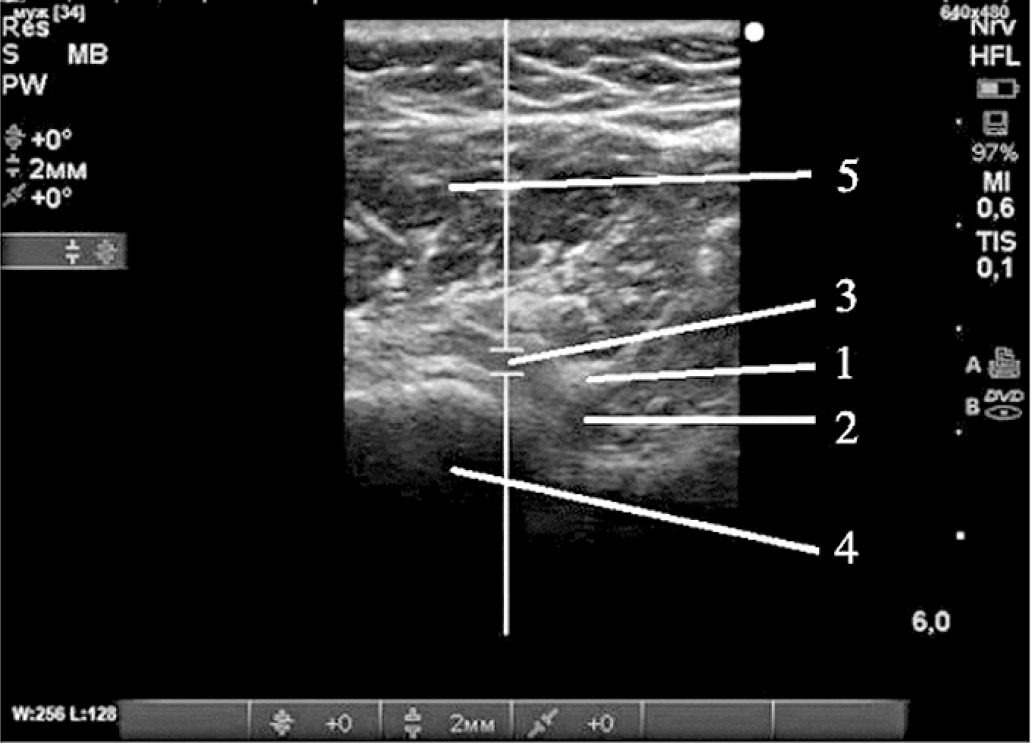

Затем, не меняя положения пациента, датчик переводили в горизонтальную плоскость в область хирургической шейки плечевой кости, добиваясь продольной визуализации задней огибающей плечо артерии и сопровождающего её подмышечного нерва (рис. 5). Идентифицировали место выхода подмышечного нерва из четырёхстороннего отверстия (рис. 6), который здесь отдает суставные ветви. Иглу вводили латеральнее датчика по длинной оси в вентро-медиальном направлении и инъецировали 5 мл 0,75% раствора ропивакаина до появления гипоэхогенной тени вокруг нерва и прекращения нейростимуляционных сокращений дельтовидной мышцы. Эффективность блокады надлопаточного и подмышечного нервов оценивали по невозможности отведения и поднятия блокируемой конечности при сохранении движений в локтевом суставе и кисти.

Рис. 5. Поперечное сканирование при включенном PW (импульсно-волновом) допплере. Идентифицирована задняя огибающая плечо артерия в месте её отхождения от подмышечной артерии

Рис. 6. Поперечное сканирование (относительно плечевой кости) на уровне четырёхстороннего отверстия: 1 – подмышечный нерв (место блокады), 2 – подмышечная артерия, 3 – задняя огибающая плечо артерия, 4 – плечевая кость, 5 – дельтовидная мышца